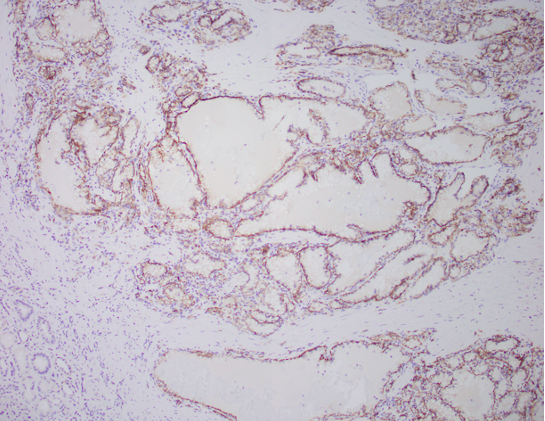

A 61-year-old female presents with a 3.5 cm renal mass. Provided are the H&E and CA9 IHC slides which show a cytoplasmic, cup-shaped distribution. CK7 shows diffuse membranous/cytoplasmic staining and AMACR and CD10 are both negative (not shown here).

Correct Answer A. This is a case of a clear cell papillary renal tumor (formerly called clear cell papillary renal cell carcinoma).

- Indolent tumor with clear glycogen-rich cytoplasm, luminal nuclear polarization, inconspicuous nucleoli, and with papillary or tubular architecture with fibrovascular stroma

- Distinctive immunohistochemical profile: positive CK7 and CAIX showing a cup-like pattern, with negative or patchy CD10 and AMACR